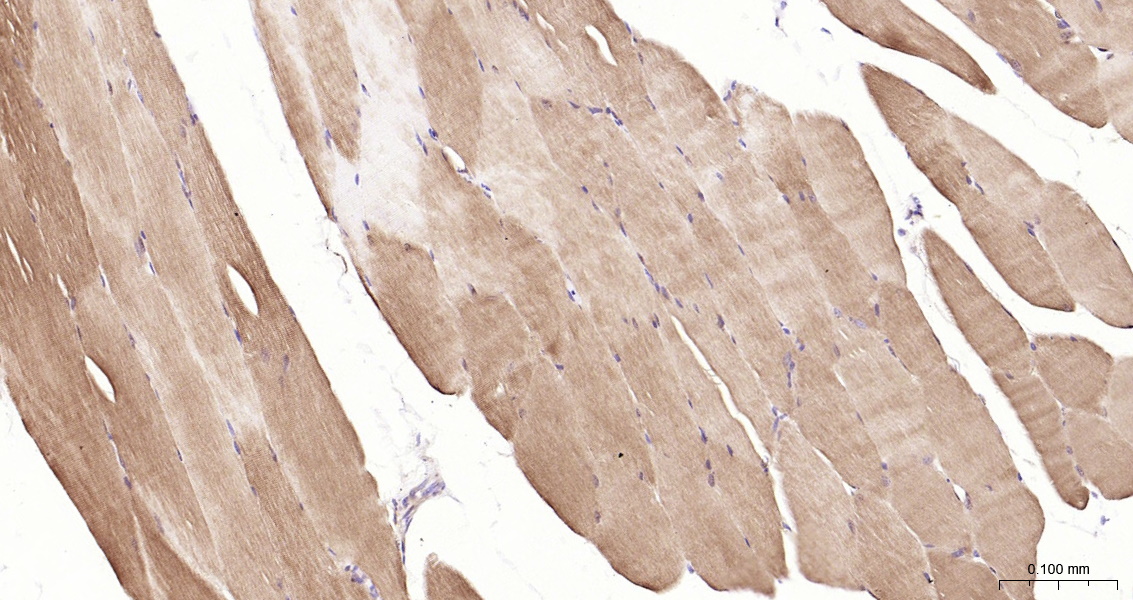

• IHC-P

IHC-P IHC-P1:50-200

IF(IHC-P) IFIHC-P1:50-200